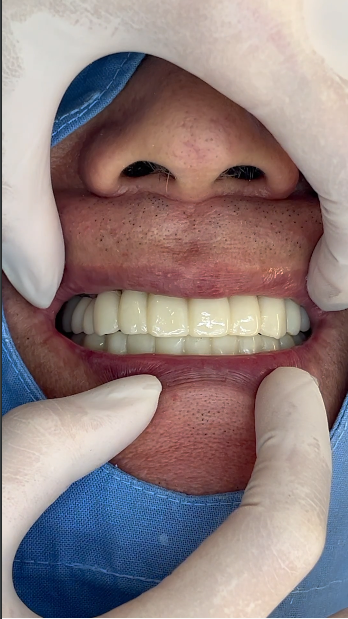

수술당일 임시치아,

하지만 그런 걱정 하나하나를 잘 해결하고 나면 치료는 생각보다 간단하고 빨리 끝날 수 있답니다. 하루에치과에서는 이런 경우 발치와 동시에 전체임플란트를 식립하고 당일에 바로 치아를 만들어 드리기 때문에 치아없이 지내는 시간이 없어요. 오히려 치료전보다 예쁜 치아를 끼고 집에 가십니다. 그래서 이미 수술하는 날 만족도가 좋습니다.